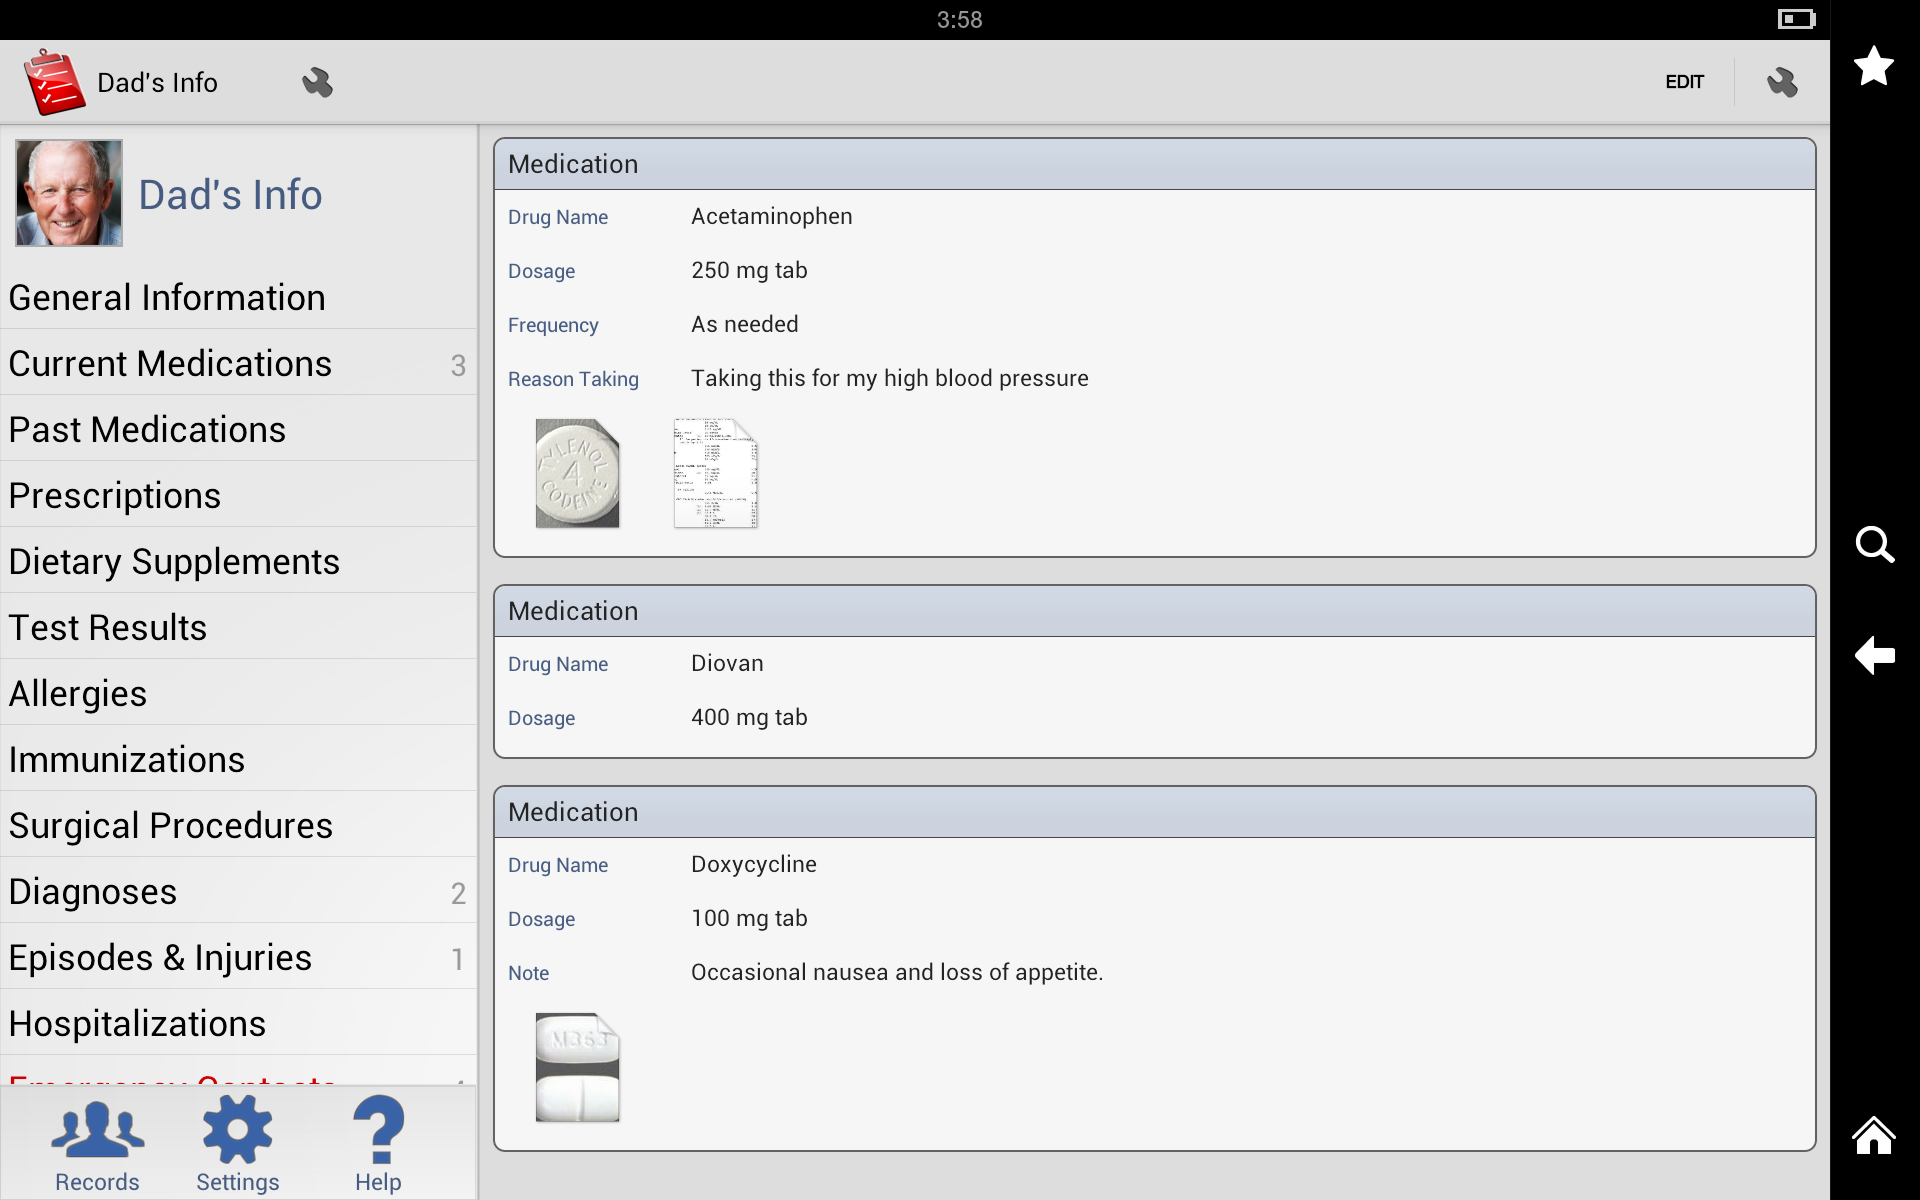

Medication List

With My Medical, you can create a comprehensive list of all the medications you take, including dosage, frequency, and any special instructions. You can set reminders to take your medications and track when you’ve taken them.

With My Medical, you can create a comprehensive list of all the medications you take, including dosage, frequency, and any special instructions. You can set reminders to take your medications and track when you’ve taken them.

User Interface

My Medical has a clean, intuitive interface that makes it easy to navigate and use. The app is organized into tabs for each section, making it easy to find the information you’re looking for. The buttons and menus are clearly labeled, and the app uses intuitive icons to represent different functions.